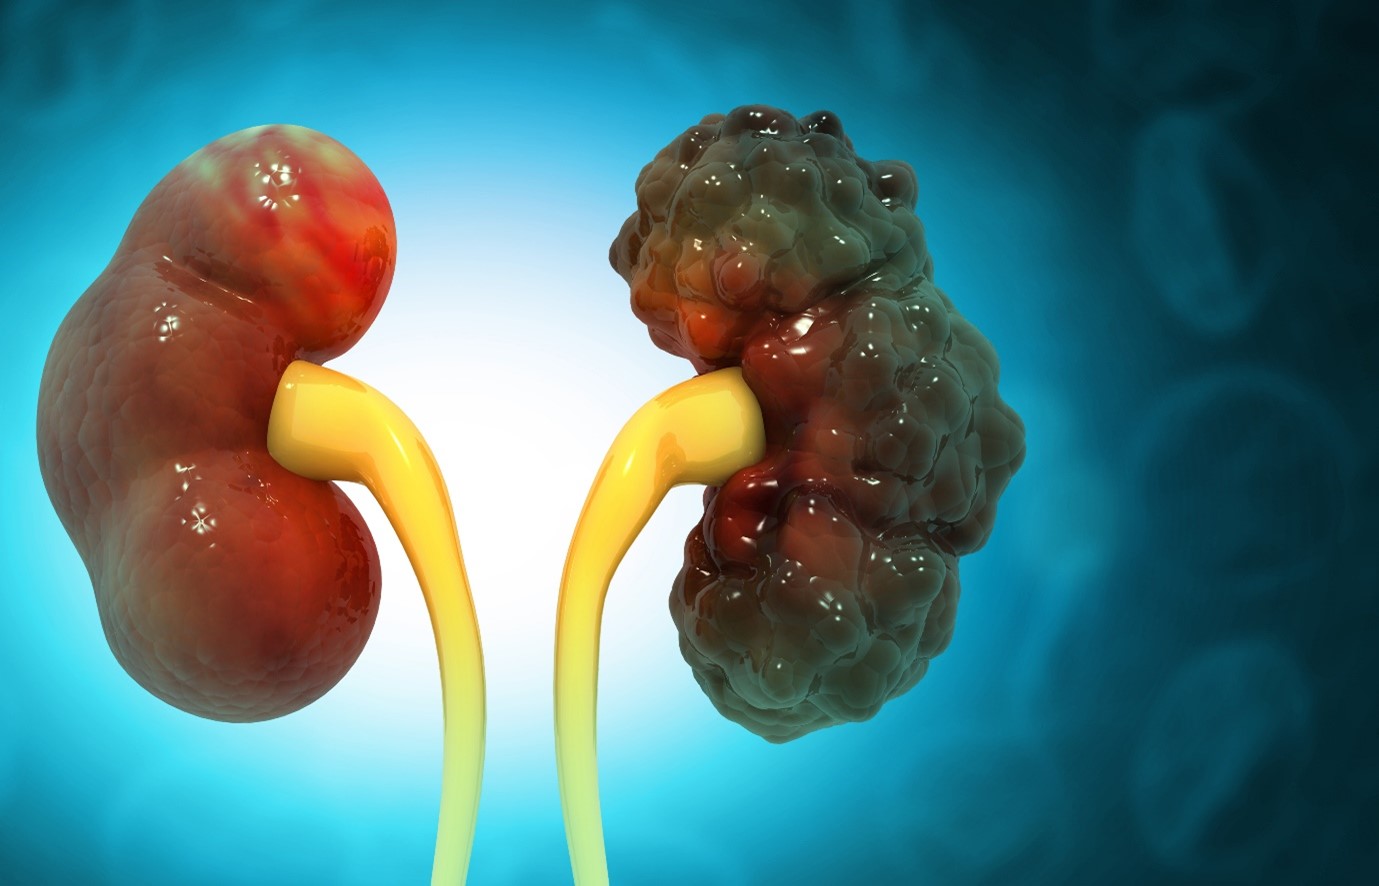

Polycystic Kidney Disease: What to Know About This Silent Disorder

What Is Polycystic Kidney Disease? PKD is a genetic condition where cysts, which are fluid-filled sacs, develop in the kidneys.

Chronic Kidney Disease (CKD) is a condition that affects the function of the kidneys. This disease can lead to kidney

The Silent Threat: Chronic Kidney Disease Symptoms You Shouldn’t Ignore

Chronic Kidney Disease (CKD) is a condition that affects millions of people worldwide. It is often referred to as a

Chronic Kidney Disease: A Guide to Understanding and Managing Your Kidney Health

Chronic Kidney Disease (CKD), also known as chronic kidney failure, is a condition characterized by the gradual loss of kidney